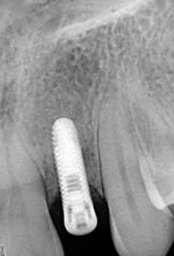

X-ray of Implant

Single Tooth Implant

X-ray of Implant + Abutment

X-ray of Implant +

Abutment + Prosthesis